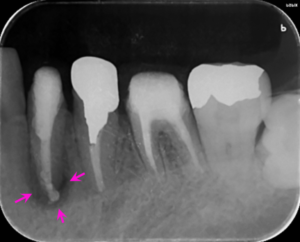

左下6番の歯の根の中を清掃し終わった後に内部に薬を詰めた直後のレントゲン写真です。

薬は根の中に緊密に詰まっています(矢印ピンク)。

左下6番の歯の根管治療終了3か月後に、左下4番の歯の根管治療を開始した後のレントゲン写真です。以前に根に詰めてあった薬を除去している途中です(矢印赤)。まだ根の先の骨の溶けている部分の大きさは変わりません(矢印ピンク)。